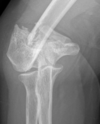

En 82- årig kvinde har pådraget sig ovenstående brud ved et kraftigt vrid i venstre ben.

Hvilket af følgende udsagn er KORREKT?

- a. Der er tale om en segmentær fraktur

- b. Frakturen vinkler lidt medialt

- c. Pga. patientens alder er den bedst behandlet med gips og kørestol indtil heling

- d. Skal behandles så man opnår primær heling

- e. Der er tale om en spiralfraktur

*e. Der er tale om en spiralfraktur

- Note:*

- a. forkert - der er kun et enkelt frakturniveau*

- b. forkert - den vinkler let lateralt (man skal kigge på distale segment)*

- c. forkert - vægtbærende og derfor osteosyntese*

- d. forkert - det er ikke en intraartikulær fraktur. Sekundær heling med callus er ok*

- e. korrekt*